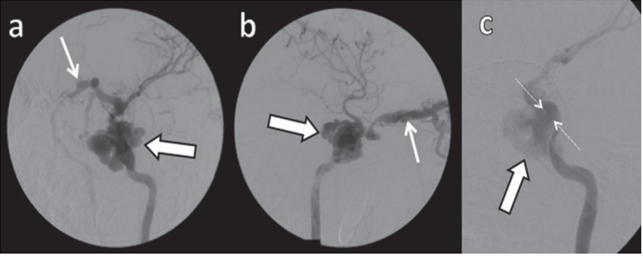

Paciente do sexo masculino, 28 anos, com antecedente de traumatismo cranioencefálico há 4 anos, passou a apresentar no último ano proptose, hiperemia conjuntival, ptose palpebral e redução da acuidade visual à esquerda, além de cefaleia. O caso foi discutido em reunião clínica multidisciplinar, na qual a equipe de Radiologia Intervencionista sugeriu a realização de angiografia cerebral. Abaixo temos algumas imagens com subtração digital (fase arterial). a: incidência oblíqua anterior esquerda. b: incidência em perfil. c: incidência de trabalho.

Assinale a alternativa que contém o correto diagnóstico deste paciente.